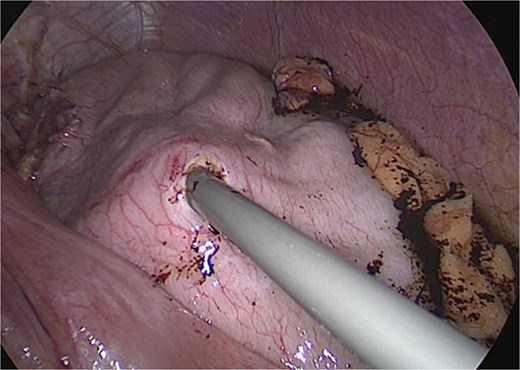

Surgical management involved reducing all herniated abdominal organs from the thoracic cavity. To address the distention of the gastric remnant, a gastrotomy was performed to evacuate the accumulated fluid (Fig. 3). This was followed by a primary hiatal repair using an anterior approach, and resection of the remnant stomach up to the level of the duodenum (Fig. 4).